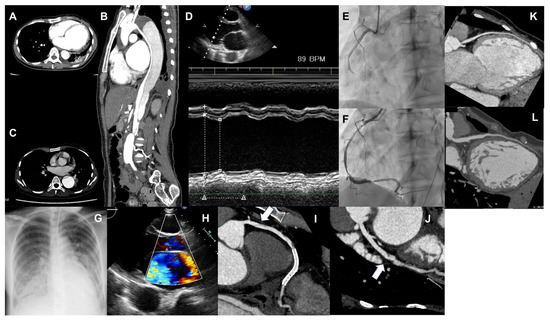

Figure 2.

(A,B) Computed tomography (CT) image showing aortic dissection. A is the horizontal section, and B is the vertical section. A false lumen is observed from the distal arch, which seems to compress the true lumen. (C) CT image of dilated aortic dissection at the distal arch, which has expanded to 50 mm, and it has been determined that distal arch replacement surgery should be performed. (D) Image of M-mode in echocardiography, showing a markedly reduced left ventricular contractility. (E,F) Coronary angiography images before and after right coronary revascularization. (E) Showing the right coronary artery is occluded at #3 due to coronary artery dissection. (F) A coronary stent being placed in #3. (G) Chest radiograph showing pulmonary edema due to heart failure exacerbation. (H) Mitral regurgitation exacerbation due to myocardial ischemia. (I) Image of coronary CT angiography of the right coronary artery. Widespread coronary artery dissection on the proximal portion (#1–#2) of the right coronary artery stent. (J) Image of coronary CT angiography of the left circumflex artery. Coronary artery dissection is newly recognized in the left circumflex (#13). (K) Image of coronary CT angiography of the left ascending artery in the first hospitalization for heart failure. (L) Image of coronary CT angiography of the left ascending artery following the development of inferior myocardial infarction. The left ascending artery is diffusely dilated as compared with that observed in Figure (K).